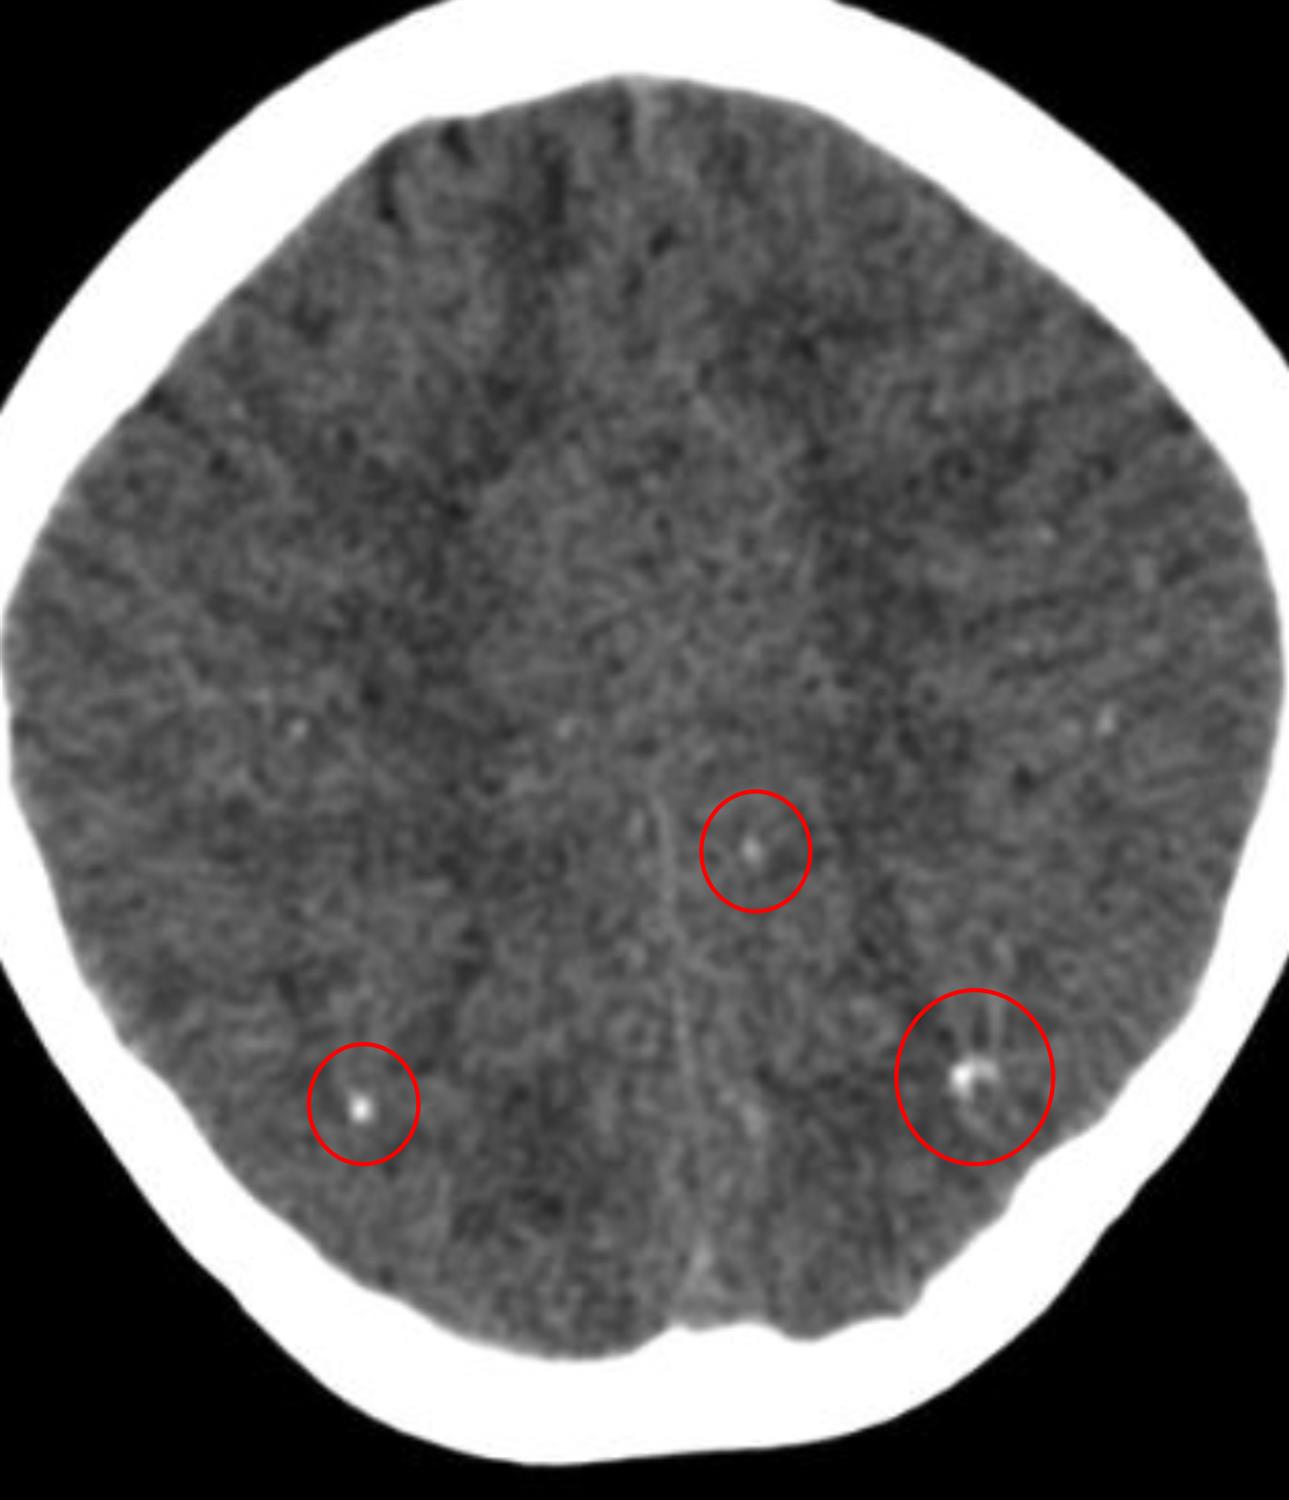

A 1-day-old boy is evaluated in the newborn nursery for several episodes of vomiting. He was born at 37 weeks gestational age to a 29-year-old woman via an uncomplicated vaginal delivery. Apgar scores were 8 and 9 at 1 and 5 minutes, respectively. The pregnancy was uncomplicated, other than a 1-week episode of low-grade fever and swollen lymph nodes early in the pregnancy. Medications during pregnancy included folic acid and a multivitamin. The mother is up to date on all immunizations. His temperature is 98.6°F (37.0°C), blood pressure is 60/40 mmHg, pulse is 140/min, and respirations are 42/min. The infant is at the 99th percentile for head circumference, 15th percentile for length, and 15th percentile for weight. He has several purpuric lesions on his trunk and extremities and a fundoscopic exam shows pigmented macular lesions. A CT scan demonstrates the findings shown in Figure A. Which of the following congenital infections is the most likely diagnosis?

This infant, who presents with a purpuric rash, chorioretinitis, signs of hydrocephalus, and diffuse intracranial calcifications on imaging, most likely has congenital toxoplasmosis infection.

Figure/Illustration A is a head CT demonstrating diffuse calcifications inside the brain parenchyma (red circles). These findings are consistent with congenital toxoplasmosis infection.